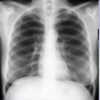

What is this CXR showing?

* Diffused Pulmonary Edema

What is the classic sign on a CXR of pulmonary edema secondary to CHF?

* Bat Wing Pattern * Enlarged Heart